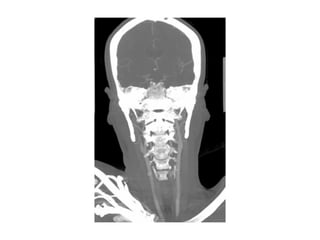

• Bilan neurovasculaire

– Imagerie des TSA dans les 24 heures après l’admission